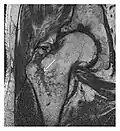

Figure 13: Partial osseous avulsion of the gluteal muscles at the greater trochanter in a 59-year-old man who presented with the right hip pain without a history of trauma. Lauenstein view and anteroposterior and radiographs (not shown) did not show an obvious fracture line or disruption of bony contours in the acetabulum or the right femoral neck. (a) Coronal T1-weighted MRI displays an incomplete fracture line extending partially from the greater trochanter (arrow). (b) Coronal short tau inversion recovery MRI shows heterogeneous hyperintensity in the same region (arrow) as well as hyperintensity within the gluteus medius and minimus muscles (arrowheads) consistent with tissue edema and hematoma.[1]

-

a -

b

Figure 14: Subcapital insufficiency fracture in a 55-year-old man with a left hip pain without a history of trauma. Anteroposterior and Lauenstein view radiographs centered on the left hip do not show an obvious fracture line, but mild acetabular osteophytosis was noted consistent with hip osteoarthritis (not shown). (a) Coronal T1-weighted MRI shows a linear low-signal band through the femoral neck corresponding to a fracture line (arrowheads). (b) Bone scintigraphy shows focal uptake (arrow) corresponding to the fracture.[1]